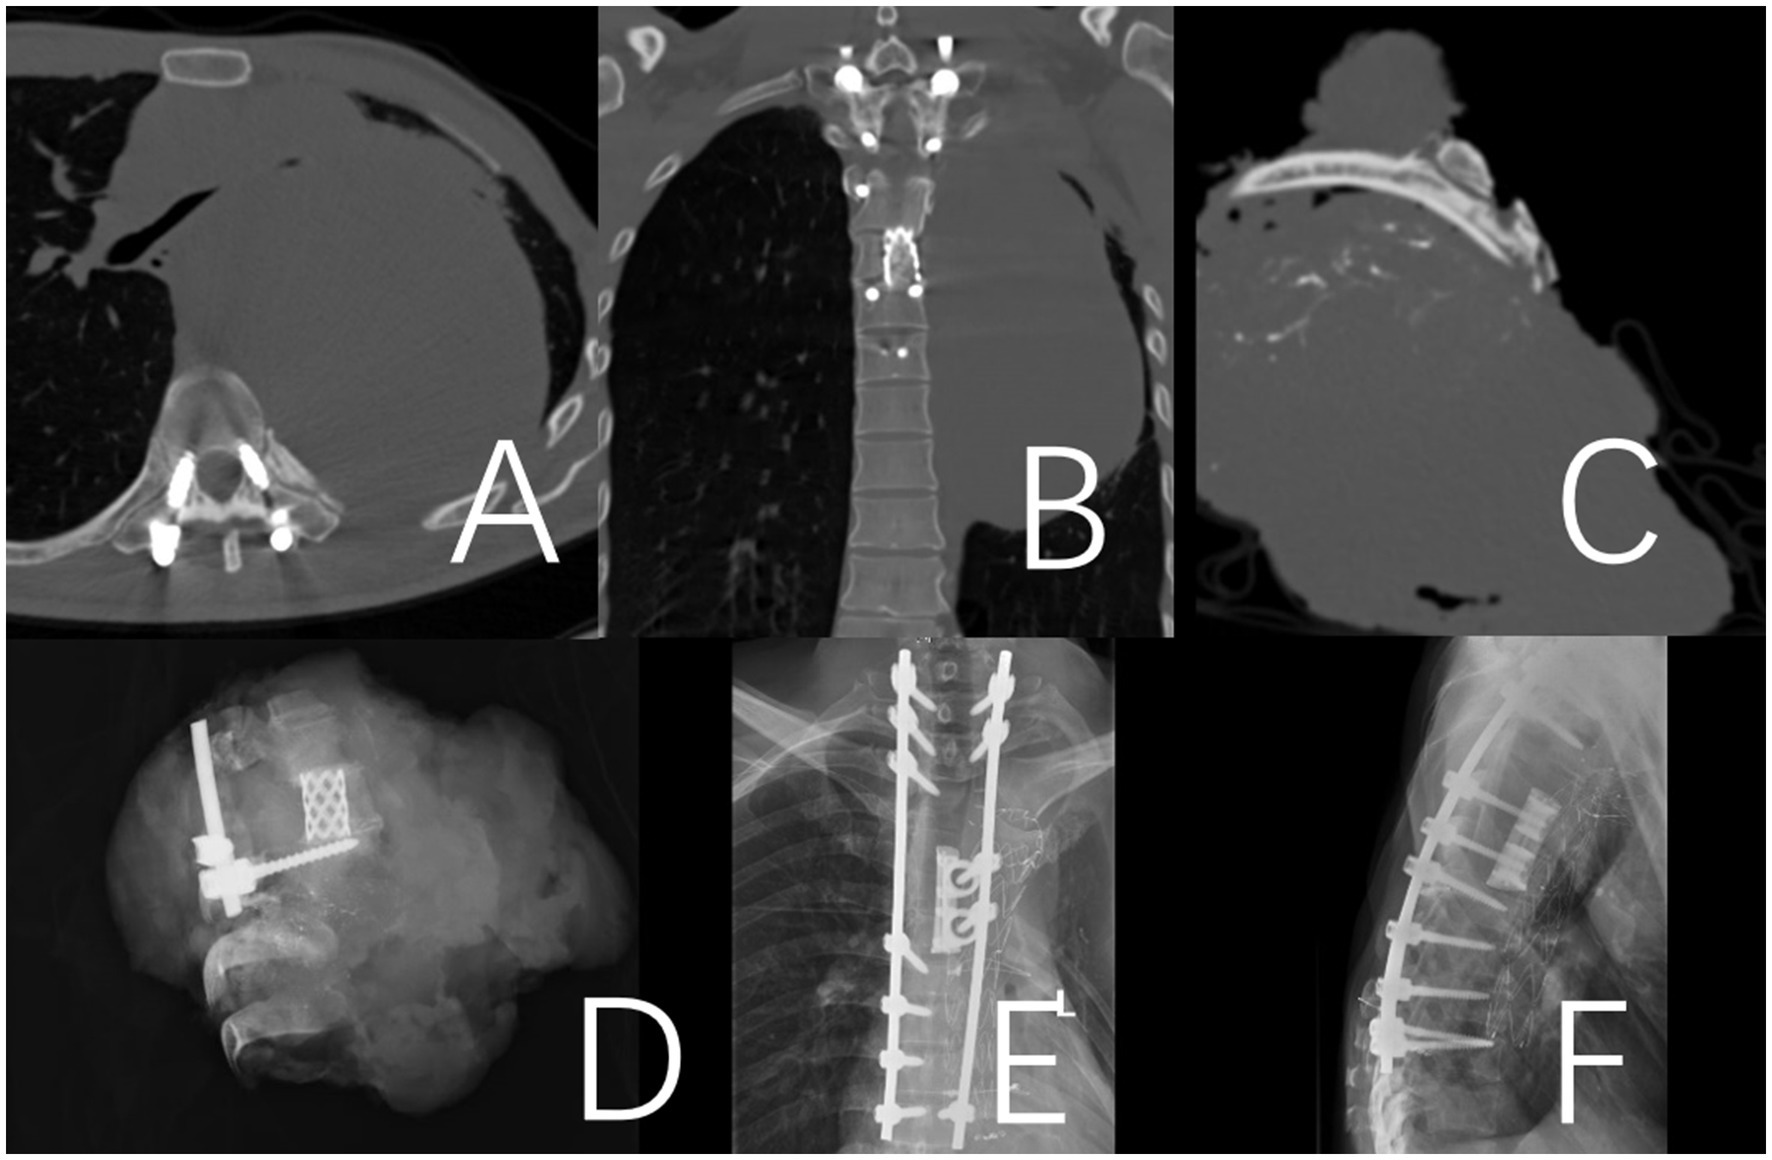

Figure 3. A 36-year-old male patient who presented with a recurrence 12 months after the initial surgery for a T2-10 spindle cell sarcoma. To address the recurrent lesion, which was primarily located at the T4-9 levels, a posterior approach T4-9 en bloc resection (partial through-tumor) and pulmonary metastasectomy were performed. A and B: Illustrate the internal fixation after revision surgery. (A,B) Preoperative CT revealed a paraspinal space-occupying lesion on the left side of the spine, which was considered malignant. (C) CT image of the surgical excision specimen. (D) X-ray image of the surgical excision specimen. (E,F) Illustrate the internal fixation after revision surgery.